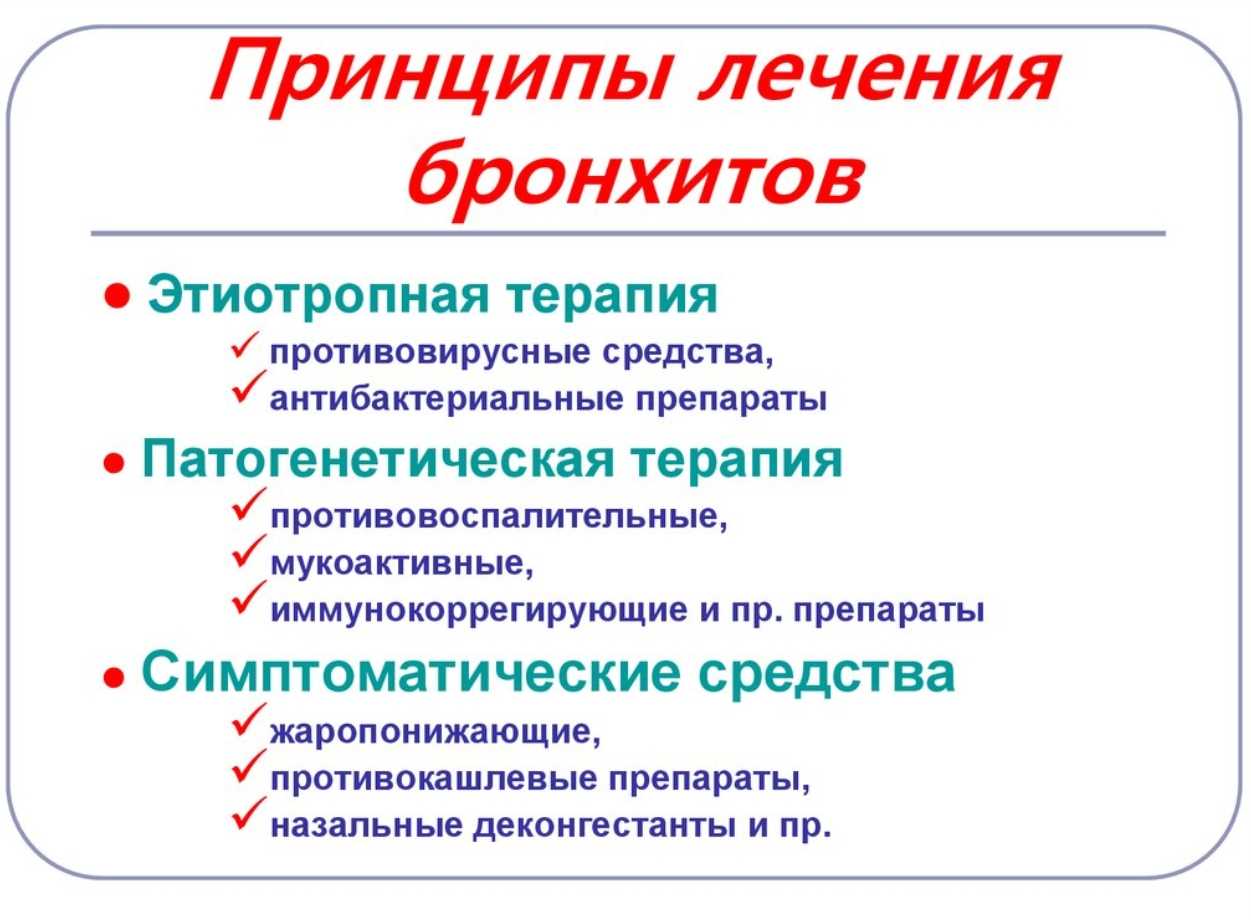

Традиционное лечение

Для лечения бронхита используют комплексную методику, куда входят медикаментозные препараты и средства, направленные на облегчение состояния. К лекарствам, которые используют для лечения бронхита у взрослых, протекающего без температуры, относятся:

- противовирусные:

- антибиотики;

- антигистаминные;

- бронхолитики;

- муколитики;

- витамины;

- иммуномодуляторы.

Какие именно группы препаратов будут использоваться, напрямую зависит от возбудителя заболевания и вида бронхита.